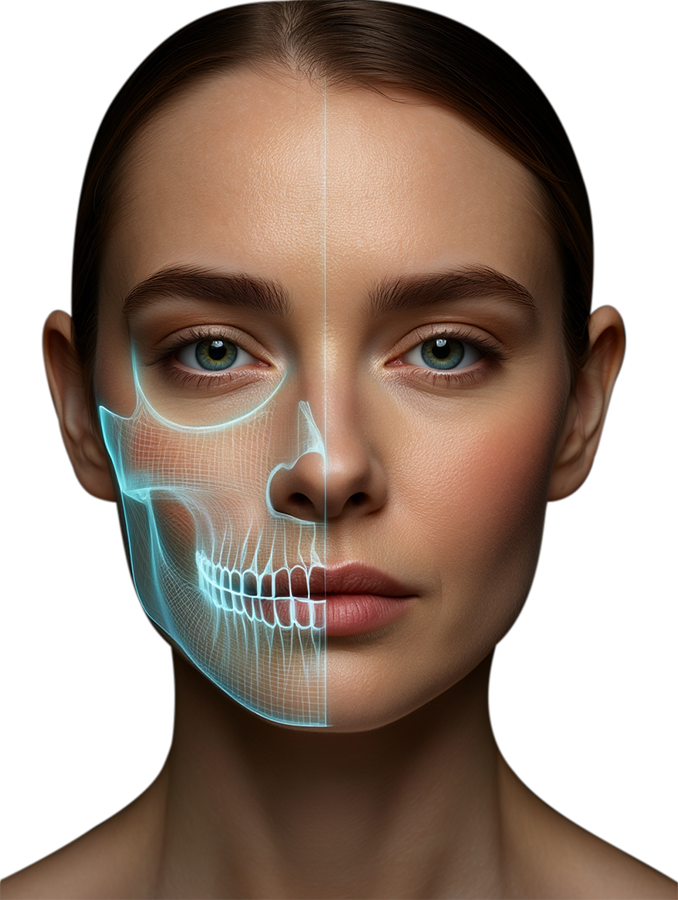

ШІ‑асистент для лікарів‑стоматологів: слухає, розуміє, документує, структурує та формує звіти автоматично.